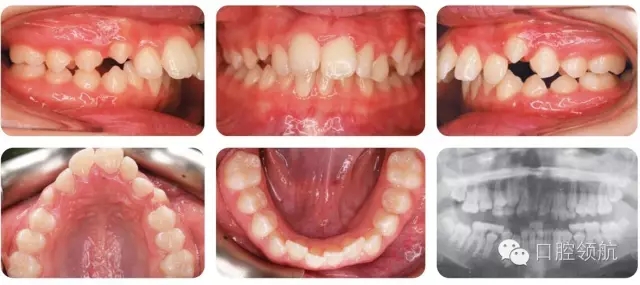

12歲的女性患者,由全科牙醫(yī)轉(zhuǎn)診。該患者健康情況良好,主訴是前牙前突(圖2.1)。

圖2.1

口內(nèi)相中的牙列處于哪一階段?

早期恒牙列。除LL7部分萌出以外,其余第二磨牙尚未萌出。

錯(cuò)牙合的主要特點(diǎn)有哪些?

● 安氏II類1分類,深覆蓋,深覆牙合,下前牙咬在上前牙腭側(cè)黏膜。

● 右側(cè)磨牙1/2牙尖Ⅱ類關(guān)系,左側(cè)磨牙I類關(guān)系。

● 中線一致。

● UL2多生牙已萌出。

雙側(cè)磨牙關(guān)系為何不一致?

左上牙列存在一顆多生牙,但中線基本一致,說(shuō)明UL6比正常位置偏遠(yuǎn)中,所以更接近I類關(guān)系而不是II類。